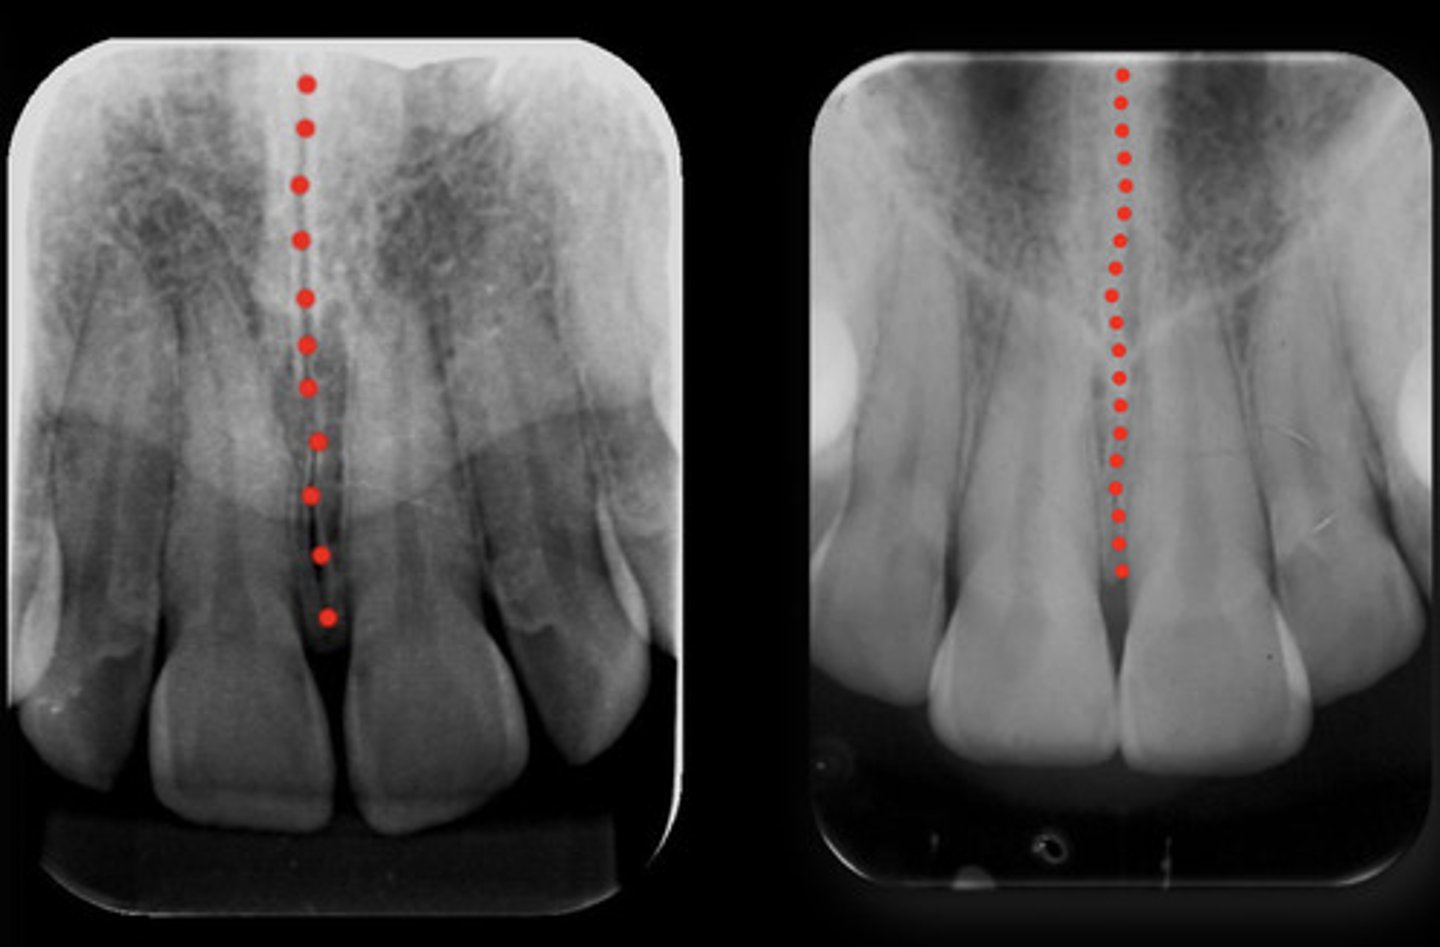

What are the red dots representing?

Dental papilla space

Dental follicle space